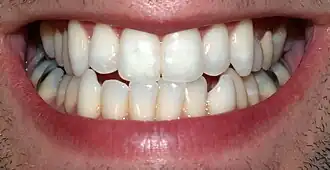

Les dents permanentes ou dents définitives sont les dents qui ne se renouvellent plus.

La denture humaine possèdent 32 dents permanentes. Les 8 incisives, les 4 canines et les 8 prémolaires remplacent les 20 dents déciduales, les prémolaires remplaçant les 4 molaires déciduales.